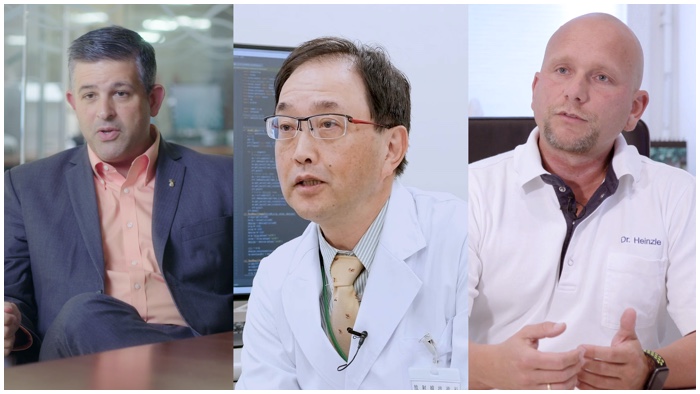

Discover the new reality of your peers

Radiologist - Imagine how your work could change from one day to the next

The Ingenia Ambition 1.5 Tesla magnet is the next generation of MR technology. It brings together the most important aspects of having a successful MR system.

Constantino Peña

Medical Director of Vascular Imaging at Baptist Hospital, Miami Cardiac and Vascular Institute

Head of Radiology - What happens when environmentally friendly also means patient friendly and time friendly?

This isn’t just something that will help us save energy. As cooling 1500 liters of helium uses a lot of energy. But this will also save us money and help us be more environmentally friendly.

Dr. Marίa del Mar Travieso

Head of Radiology Department, Hospitales San Roque, Spain

Technologist - It’s possible to have reassurance and workflow support

There are lots of applications that can improve the workflow. Like Compressed SENSE, VitalEye and VitalScreen. We feel that this system combines both safety and improved workflow.

Shibukawa

Radiologist Technician, Tokai University, Japan